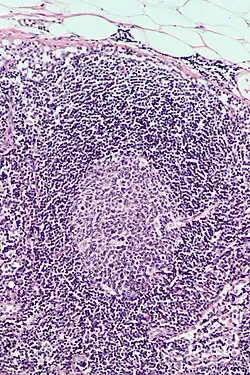

Follicular hyperplasia (FH) is a type of lymphoid hyperplasia and is classified as a lymphadenopathy, which means a disease of the lymph nodes. It is caused by a stimulation of the B cell compartment and by abnormal cell growth of secondary follicles. This typically occurs in the cortex without disrupting the lymph node capsule.[1] The follicles are pathologically polymorphous, are often contrasting and varying in size and shape.[2] Follicular hyperplasia is distinguished from follicular lymphoma in its polyclonality and lack of bcl-2 protein expression, whereas follicular lymphoma is monoclonal, and expresses bcl-2.[3]

Follicular hyperplasia can be distinguished among other diseases by observing the density of a lymph follicle on low magnification. Lymph nodes with reactive follicles contain extensions outside its capsule, follicles present throughout the entire node, obvious centroblasts and the absence or diminishing mantle zones. Immunohistochemistry can help distinguish a difference between a patient with follicular lymphoma to follicular hyperplasia.[1] Reactive follicular hyperplasia does not express BCL2 proteins in B cell germinal centers and are absent light chain reaction in immunostaining and flow cytometry as well as absent IG rearrangements.[1]

BCL2 protein expression is usually absent in follicular hyperplasia but prominent in follicular lymphomas. A comparison with other stains that include germinal center markers such as BCL-6 or CD10 is useful to compare when determining a proper diagnosis.[1] CD10 positive cells are metalloproteinase which activate or deactivate peptides through proteolytic cleavage.[9]